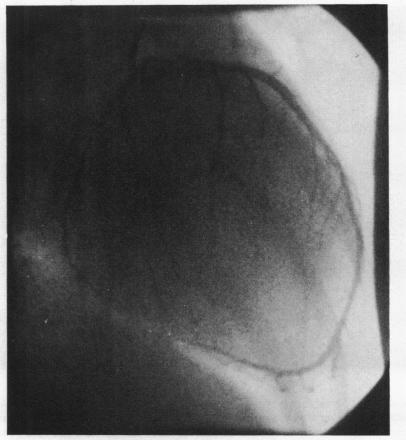

Selective coronary angiography in primary myocardial disease.

Br Heart J. 1973 Feb;35(2):165-73. doi: 10.1136/hrt.35.2.165.